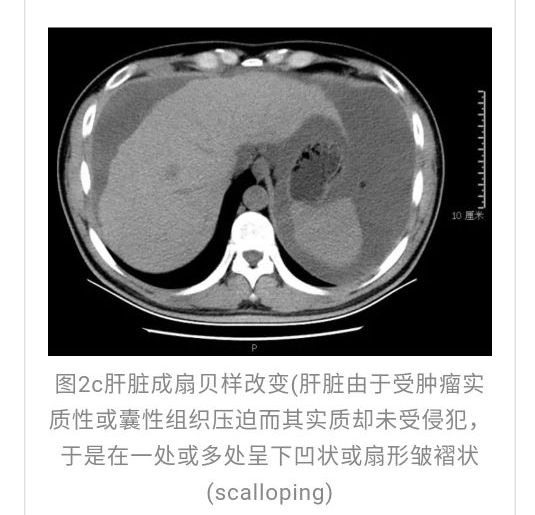

全腹CT:(1)结合病史考虑腹膜炎(见图2A),大量腹水;(2)右骼窝区管状样结构,考虑阑尾扩张(见图2B);(3)肝脏多发小囊肿(见图2C);(4)肝内胆管轻度扩张,建议隔期复查。

本例确诊后对B超及CT再次回顾发现:腹腔、盆腔可见不均质中强回声包块,部分呈囊实状,腹膜增厚,大网膜成饼状(如图2A)和肝周可见不均质中强回声弧形压迹、脾周可见不均质中强回声包饶,肝脏成扇贝样改变(如图2C),但在诊断报告中未提及。有学者发现mantle和scalloping(如图2A,2C)在PMP中具有代表性,且mantle较scalloping更为常见,若mantel征同时伴有大小不一的囊性改变,则更具诊断价值。

与此同时,还应与肝硬化腹水、妇科肿瘤、肠梗阻等疾病相鉴别。此患者为男性,全腹CT及PET-CT均提示阑尾扩张,很大可能来源于阑尾黏液性肿瘤。阑尾黏性肿瘤早期可无任何症状,随着瘤体堵塞阑尾,累及浆膜下层,播散至腹盆腔,可形成大量的黏液性腹水,又称“胶腹”,则可出现腹痛、腹胀、腹围增加等症状。通过本病例分析认为此类患者,腹穿时若发现腹水不易抽出或抽出物为黏稠胶冻样,腹部B超提示液性暗区内有漂浮的团状回声有分隔,撞击腹部后可出现“礼花”样改变,肝脾包膜完整不光滑,有弧形压迹,全腹部CT示弥散占位,可见mantle和scallping征、大网膜成饼状且阑尾扩张应高度怀疑本病。